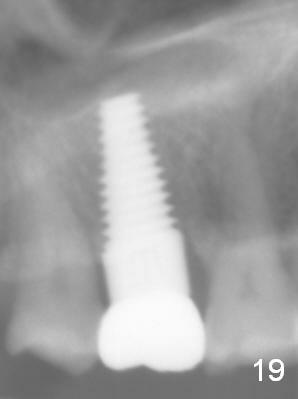

Osteotomy for immediate implant is initiated with a 2 mm pilot drill (Fig.6b red arrow) in the coronal end of the buccal slope of the septum (center of the socket). Once the drill gets initial penetration, the trajectory changes to the long axis of the tooth (Fig.6c). Then PA is taken with a parallel pin (Fig.7). It appears that the depth is not enough; there is bone apical to the pin. As osteotomy increases in diameter, burs may be deviated buccally due to the septal buccal slope (to be discussed below). With longer osteotomy, the deviation may be less. Osteotomy is deepened (Fig.6d). From this moment on, nose blowing test is done after each step. The result is all negative. As drill diameter increases, they do deviate buccally (Fig.6e arrow), since there is less bone contact buccally than lingually (compare Fig.6e,f). With the same reason, smaller tapered taps (Fig.6g pink, 5 and 6 mm) tend to be mobile buccally (arrow). When a large tap (7 mm) is inserted (Fig.8), there is no buccal mobility. It appears that the tap contacts more of the buccal plate (Fig.6h), but the coronal end of the tap is buccal (Fig.6i, pink circle). At each step of osteotomy, the coronal end of a bur or tap should be pushed as lingual as possible so that the final tap is favorable for restoration (Fig.6j). Sinus lift is done (Fig.6k red circle; Fig.9 *) before placement of 7x17 mm implant (I, >60 Ncm). Since the palatal socket is not associated with implant stability, it is closed by collagen plug (Fig.6l, blue area). As extra precaution, bone graft is placed around the coronal portion of the tissue-level implant (Fig.6l red circles), followed by collagen dressing.

The patient returns for unknown pain on the right side 1.5 years post cementation (Fig.18,19). The gingiva is healthy. Two months later, the tooth #3 is found to have fractured.